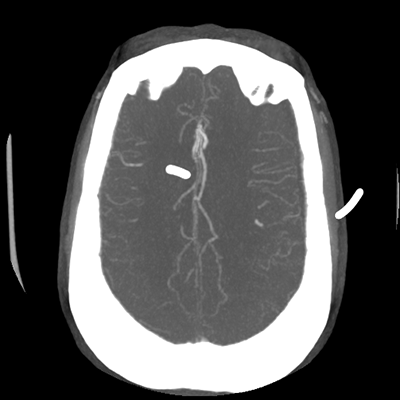

CTA head (MIP)

Starting with the non-contrast head CT, we can appreciate that there's actually not much residual subarachnoid blood at all; it's essentially all resorbed already (and cleared through the EVD). The ventricular caliber is stable. With the CTA head (for convenience's sake, the MIPs were shown), it's subtle, but we can see that the PCAs on each side are not as smooth and regular. The right MCA, starting at the bifurcation, also becomes narrower. This is [radiographic] vasospasm. Now, looking at the CT perfusion-- specifically, the Tmax (MTT) map that were selected-- there's clearly some abnormality within the bilateral cerebellar hemispheres and occipital lobes. Not a lot, but it's there. Delving further into this map, we can appreciate that the areas of abnormality are mainly green, signifying that these areas have Tmax > 6 seconds. This is the threshold that is specific, not sensitive, for vasospasm.

Putting this all together, we have thus identified radiographic vasospasm with the vessel imaging, with perfusion abnormalities that are concordant with it. Does the area of vasospasm and hypoperfusion correlate with the patient's clinical exam?